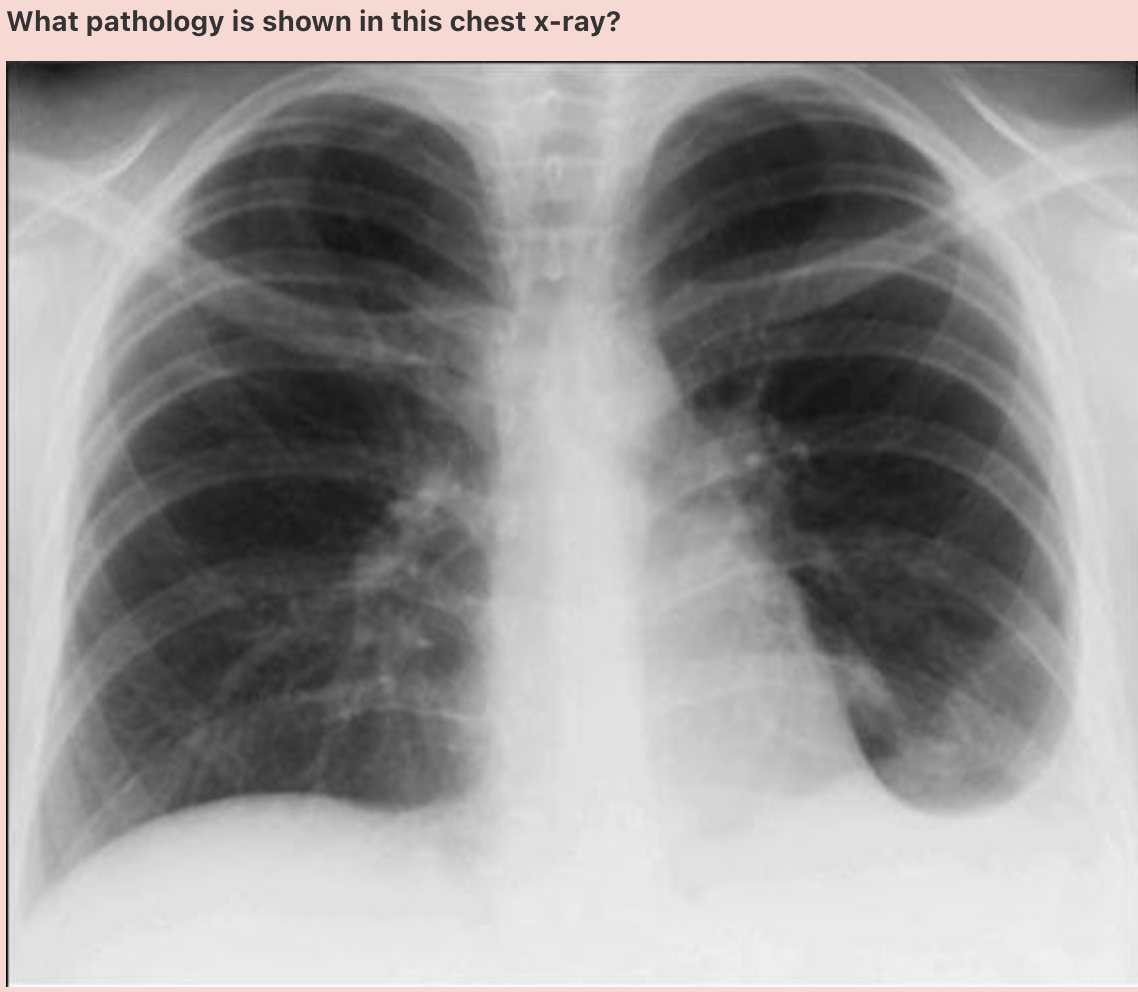

Answer: Chronic Obstructive Pulmonary Disease

In normal subjects, the diaphragm is intersected by the 5th to 7th anterior ribs in the mid-clavicular line - in this patient you can count up to 9 ribs before reaching the diaphragm - > hyperexpanded lungs.

Flattening of the diaphragm is also observed in this x-ray which is a reliable feature of lung hyperexpansion.